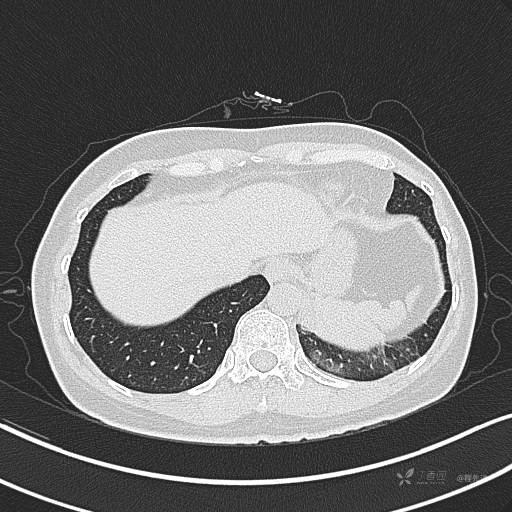

CT平扫

肺窗